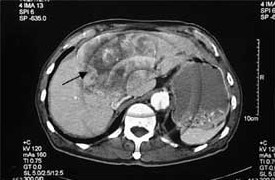

SIR therapy is usually given once and the patient is observed for response. For those who fail to respond, the treatment does not preclude them from considering other forms of treatment such as chemotherapy, radio frequency ablation and chemo-embolisation. If the patient has responded then no further SIR therapy is required. At some future date if the liver cancer recurs or starts growing again the SIR therapy can be repeated. How long the response will last is difficult to predict. Each patient behaves differently. The duration can stretch from 6 months to several years after one single SIR therapy (Figure 2).

Figure 2. Huge liver cancer (black arrow) in an 83 year old man. One year after SIR therapy, the liver cancer has 'liquefied' (white arrow). The patient is still alive 4.5 years later after ONE dose of Yttrium 90 microspheres.